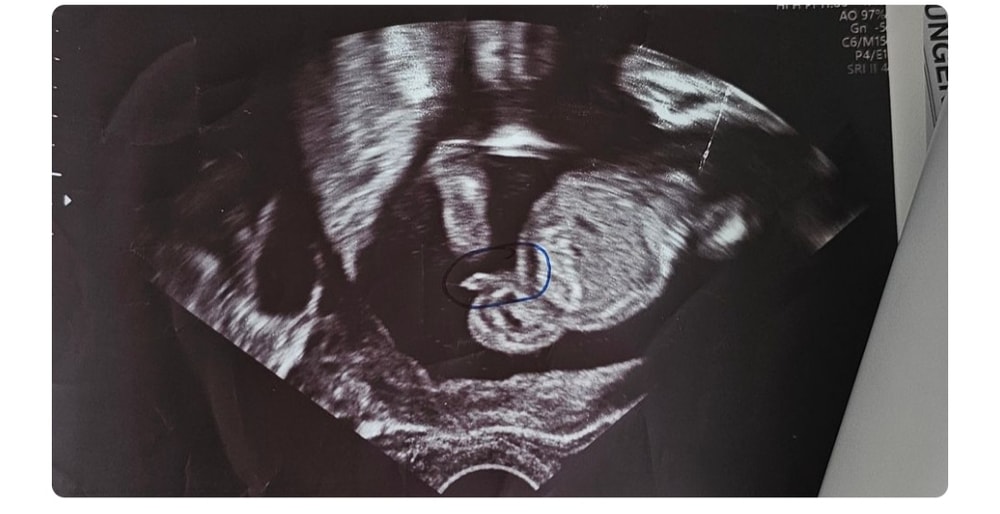

Яна , здесь 16 недели мальчик сказали на 100% Изображение

Zaynab, вот и все прелести 😄

Яна , куда пропал тогда этот прелесть 😁

Zaynab, может спрятал? Зажал?

Zaynab, ну тут очевидно мальчик 😆

Zaynab, я верю в то, что член мог завернуться куда-то в бок и не показаться на узи, потому девочку подумали )